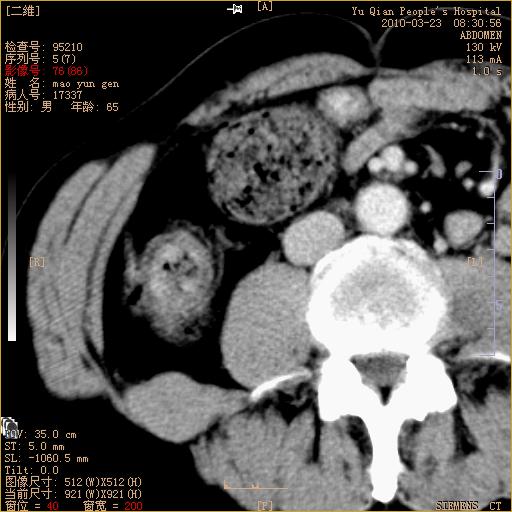

标题: CT25266:消瘦月余,前来肝部检查,请看看肠腔 [打印本页]

标题: CT25266:消瘦月余,前来肝部检查,请看看肠腔

肝区结肠占位,腺癌可考虑,建议肠镜活检。

升结肠肠壁增厚,不均强化,考虑升结肠腺癌可能性,建议肠镜检查。

1)考虑升结肠癌。2)右肾小囊肿。